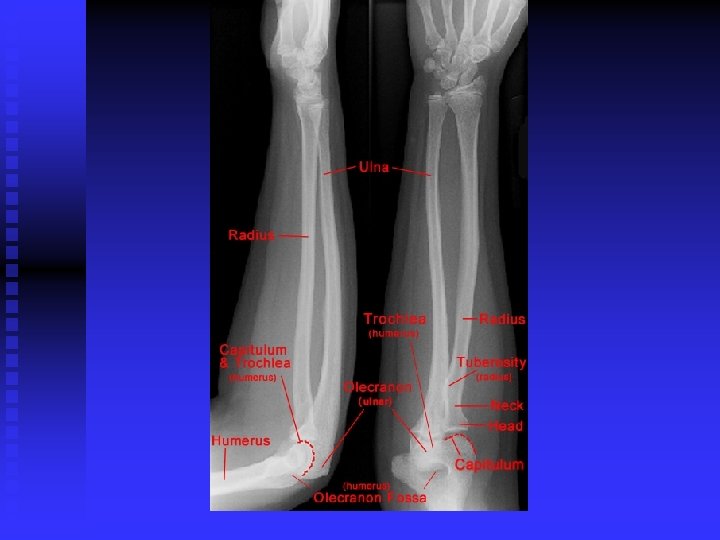

Elbow

Lateral Epicondylitis (tennis elbow) n Pathology u 30 – 50 years old u Repetitive micro-trauma u Chronic tear in the origin of the extensor carpi radialis brevis

Lateral Epicondylitis (tennis elbow) n Mechanism of Injury u Overuse syndrome caused by repeated forceful wrist and finger movements u Tennis players u Prolonged and rapid activities

Lateral Epicondylitis (tennis elbow) n Clinical Signs and Symptoms u Increased pain around lateral epicondyle u Tenderness in palpation CET u Tests t AROM; PROM t Resisted tests t Lidocaine

Medial Epicondylitis (golfer’s elbow) n Pathology u 30 - 50 years old u Repetitive micro trauma to common flexor tendon

Medial Epicondylitis (golfer’s elbow) n Mechanisms of injury u Throwing a baseball u Racquetball or tennis u Swimming backstroke u Hitting a golf ball

Medial Epicondylitis (golfer’s elbow) n Clinical signs and symptoms u Increased pain over medial epicondyle u Tenderness on palpation CFT u Tests t AROM; PROM t Resisted tests t Lidocaine

Ulnar Neuritis n Pathology u Superficial position at the elbow u Excessive pressure in this area u Second most common entrapment neuropathy in the upper extremity

Ulnar Neuritis n Mechanism of injury u Compression of the ulnar nerve: cubital tunnel (epicondyle, olecranon, MCL, arch of arcuate ligament and of 2 heads of FCU u Elbow flexion tightens arch u Repeated rapid activities such as throwing and prolonged flexion may traction or compress nerve u Nerve can sublux out of tunnel

Ulnar Neuritis n Clinical signs and symptoms u Sensory changes in classic ulnar distribution: little finger and ulnar side of ring finger u Positive elbow flexion test u Positive Tinel’s test u Weakness of grip u Deterioration of 2 point discrimination u Adductor Pollicus neuro-weakness u Neuro-weakness interossei (Wartenburg)

Ulnar Neuritis n Common treatments u Non-operative: rest is imperative; NSAIDS; determination of cause and elimination of it u Surgical intervention: decompression or transposition

Medial Overload Syndrome in Throwers n Pathology u Lateral joint line- compressive forces u Shear forces posteriorly in olecranon fossa u Tensile forces along medial joint line

Medial Overload Syndrome in Throwers n Clinical signs and symptoms u Persistent medial elbow soreness u Arm fatigue is the 1 st indicator of impending injury u Medial tenderness u Elbow pain

Medial Overload Syndrome in Throwers: Treatment Pre throwing stretches u Adequate gentle warm up with gradual increase to higher velocity throws u Post throwing stretching u ICE after throwing u Surgical Intervention u

Anterior Interosseus Nerve Syndrome (Median Nerve) n Pathology u Areas of possible compression t Between the head of the pronator teres t The proximal tendon of flexor digitorum superficialis

Anterior Interosseus Nerve Syndrome n n Mechanism for Injury u Repetitive elbow flexion with forearm pronated u Tendinitis of deep head of pronator secondary to heavy lifting u Fractures or D/C of ulna or radius Clinical Signs and Symptoms u Pain u No sensory complaints or losses u Significant muscular weakness: loss of tip to tip pinch

Radial Tunnel syndrome/Posterior Interosseous Syndrom n Pathology u Radial nerve compressed: In the proximal radial tunnel anterior to the head of the radius where nerve supplies brachioradialis and ECRL, between the ulnar half of the ECRB and its fascia, and at the distal border of supinator. t Often mimics tennis elbow t

Signs and Symptoms n n n Classic S&S of lateral epicondylitis including pain on ROM and resistive testing; resisted supination > wrist ext. Maximum tenderness should be over the supinator muscle; 4 fingers breadth distal to the lateral epicondyle Pain can radiate up and down arm Weak grip Diagnostic local anesthetic block to CET